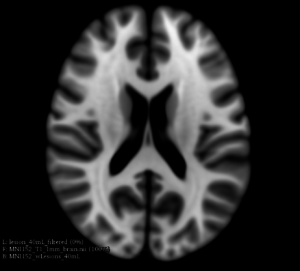

This extension offers a set of tools for brain lesion simulation, based on MRI images. At the moment, the module MS Lesion Simulator is available, where it can simulate both baseline scan lesion volumes (given a lesion load) and longitudinal image simulations. In summary, a statistical lesion database is generated based on a set of manual lesion mark-ups, being non-linearly registered to MNI152 space (isotropic 1mm of voxel resolution), and a local contrast ratio is applied on each imaging modality provided by the user. Using a small set of parameters (lesion load, lesion homogeneity, lesion intensity independence and lesion variability), it is possible to generate a broad range of MS lesions patterns in multimodal MRI imaging techniques (at moment, T1, T2, T2-FLAIR, PD, DTI-FA and DTI-ADC images are provided). For more details about this project, please see the original paper.